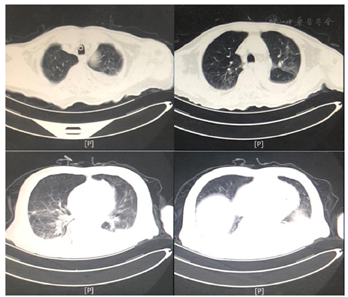

患者医学影像学检查如图1,图2,图3,图4,图5,图6,图7,图8所示,实验室检查结果如图9,图10,图11所示。

2021年3月24日患者出现顽固性低氧血症,血D2-二聚体:12810.00 ng/ml,CTPA显示肺动脉分支栓塞,双下肢静脉彩超:双下肢静脉血栓形成。加用抗凝治疗,调整康复治疗方案:(1)吸氧,监测血氧饱和度下完成康复训练项目;(2)依据患者耐受调整康复训练项目;(3)加强床旁呼吸功能训练。经上述治疗后,患者血氧饱和度有所上升,痰量有所下降,吸痰次数减少。结合患者肺部状况改善的情况给予佩戴说话瓣膜,约4 h/d,同时行语音训练,患者发音逐渐较前稍清晰,痰液可经口咳出,但仍有大量痰液瘀滞于咽部,需要辅助清除,血氧饱和度为85%~95%。2021年5月11日突发寒战、高热、皮肤花斑、咳嗽、大量咳痰,氧饱和度下降至60%。血象、感染相关指标升高;胸部CT:双肺炎症较前加重,双肺间质性病变;支气管三维重建:气管、支气管内分泌物,下叶各段支气管开口显示不清;痰培养:铜绿假单胞菌。经美罗培南抗感染治疗,并加强化痰、气管管理,加强翻身、拍背、排痰宣教后,患者未有发热,咳嗽、咳痰较前好转、感染指标正常;复查支气管三维重建:气道结构通畅;指脉氧饱和度:88%~97%。

高龄85岁患者,因碰撞致摔倒左侧股骨颈骨折,出现跌倒综合征,且早期外院诊疗期间未有康复早期介入出现多种并发症,入住我科后针对患者的肺功能、认知功能、运动功能、吞咽功能等行全面评估及临床症状的全面检查,依据评估结果及影像学实验室检查结果给予全面诊疗。肺部经美罗培南抗感染治疗,并加强化痰、气管管理,加强痰液体位引流、翻身、拍背、排痰宣教、肺功能训练等,患者未有发热,咳嗽、咳痰较前好转、感染指标正常;复查支气管三维重建:气道结构通畅;指脉氧饱和度:88%~97%。经综合临床及康复治疗后患者肺部感染控制,可耐受封堵气管套管4 h,无明显气管症状;可完成床上翻身,部分辅助下卧坐转移;坐位平衡能力达3级;看护下助行架辅助下完成室内短距离步行。